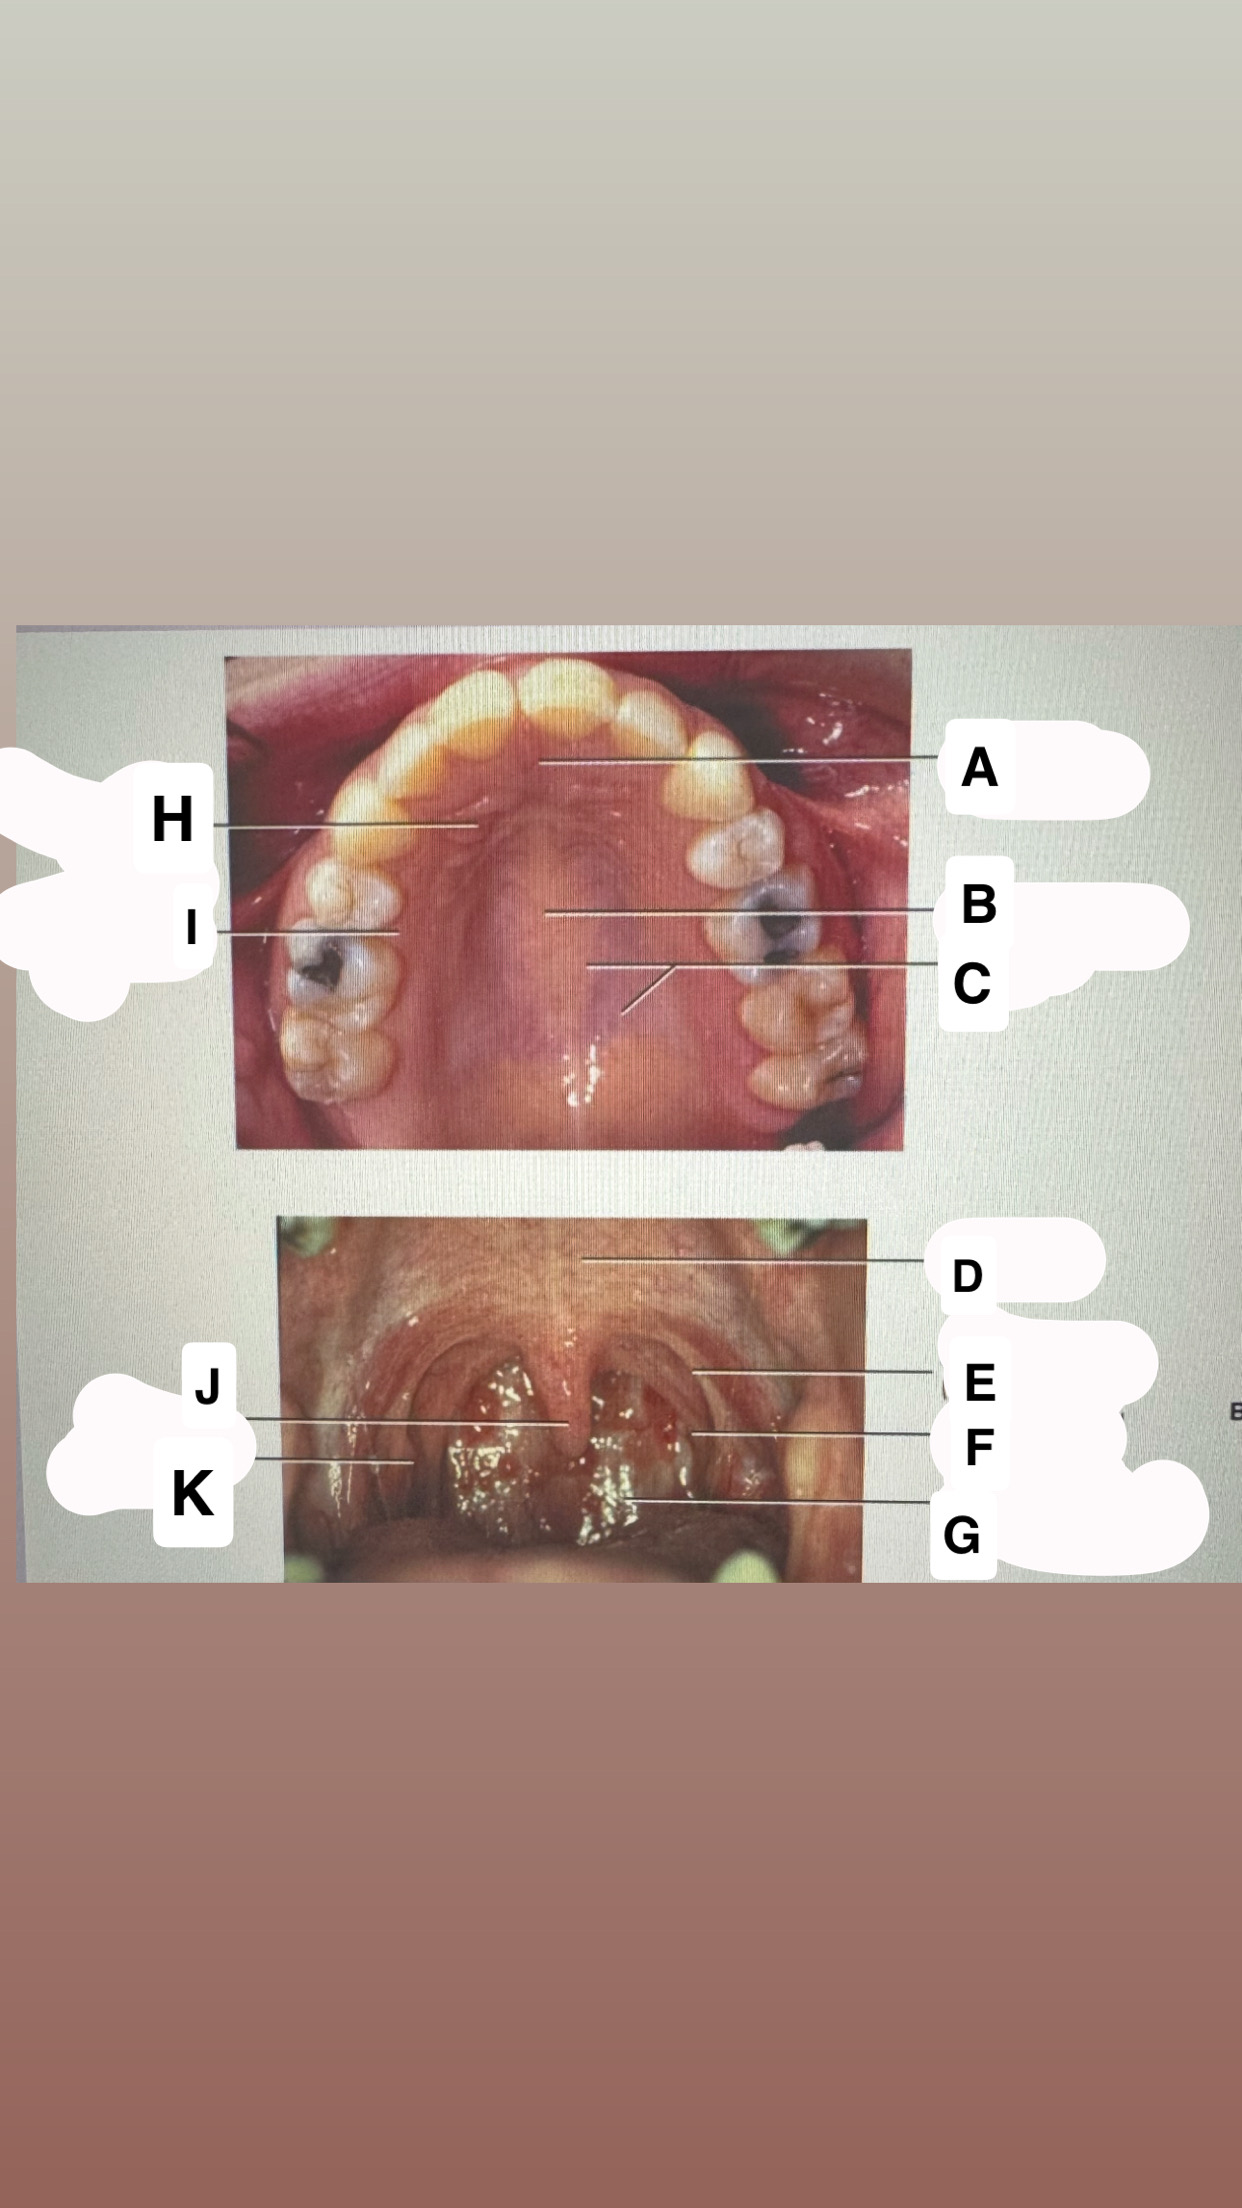

<p>Identify A</p>

buccal frenum

Mucogingival

junction

<p>Identify B</p>

Alveolar

mucose

<p>Identify C</p>

Maxillary labial frenum

<p>Identify D</p>

Marginal gingiva

<p>Identify E</p>

Maxillary vestibule

<p>Identify F</p>

Mandibular vestibule

<p>Identify G</p>

Mandibular buccal frenum

<p>Identify H</p>

Interdental-gingiva

<p>Identify I</p>

Attached gingiva